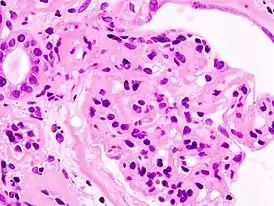

Характерен для поражения клубочкового аппарата почек.

Гистологическая классификация

| Болезнь минимальных изменений | Фокальный сегментарный гломерулосклероз | Мембранозная нефропатия | Мембранопролиферативный гломерулонефрит | ||||||||||||||||||||||||||||||||||||||